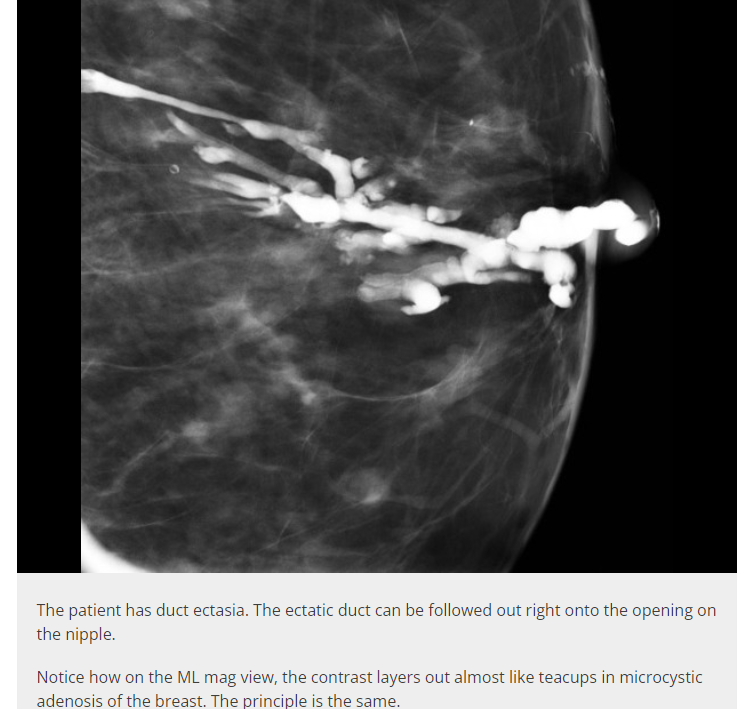

How does mammary duct ectasia present on mammogram? [1]

Microcalcifications are a key finding to remember on a mammogram, although they are not specific to mammary duct ectasia.